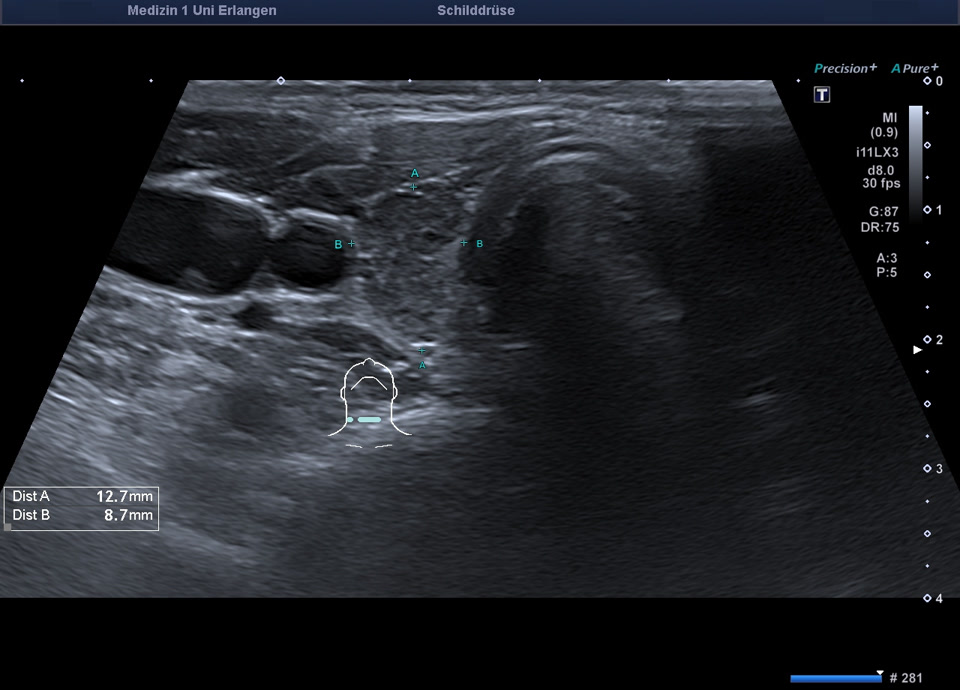

36-year-old patient with tremor, tachycardia, exophthalmos, and weight loss. Thyroid ultrasound shows bilaterally hypoechoic, inhomogeneous parenchyma with a total volume of 20.5 ml. Color Doppler sonography shows hypervascularization. Laboratory results: basal TSH decreased, T3/fT4 elevated, TRAK positive, consistent with Graves’ disease. Symptoms resolved under treatment with thiamazole and propranolol. At follow-up two years later, sonography showed a hyperechoic minimally inhomogeneous parenchyma with normal volume (15 ml).